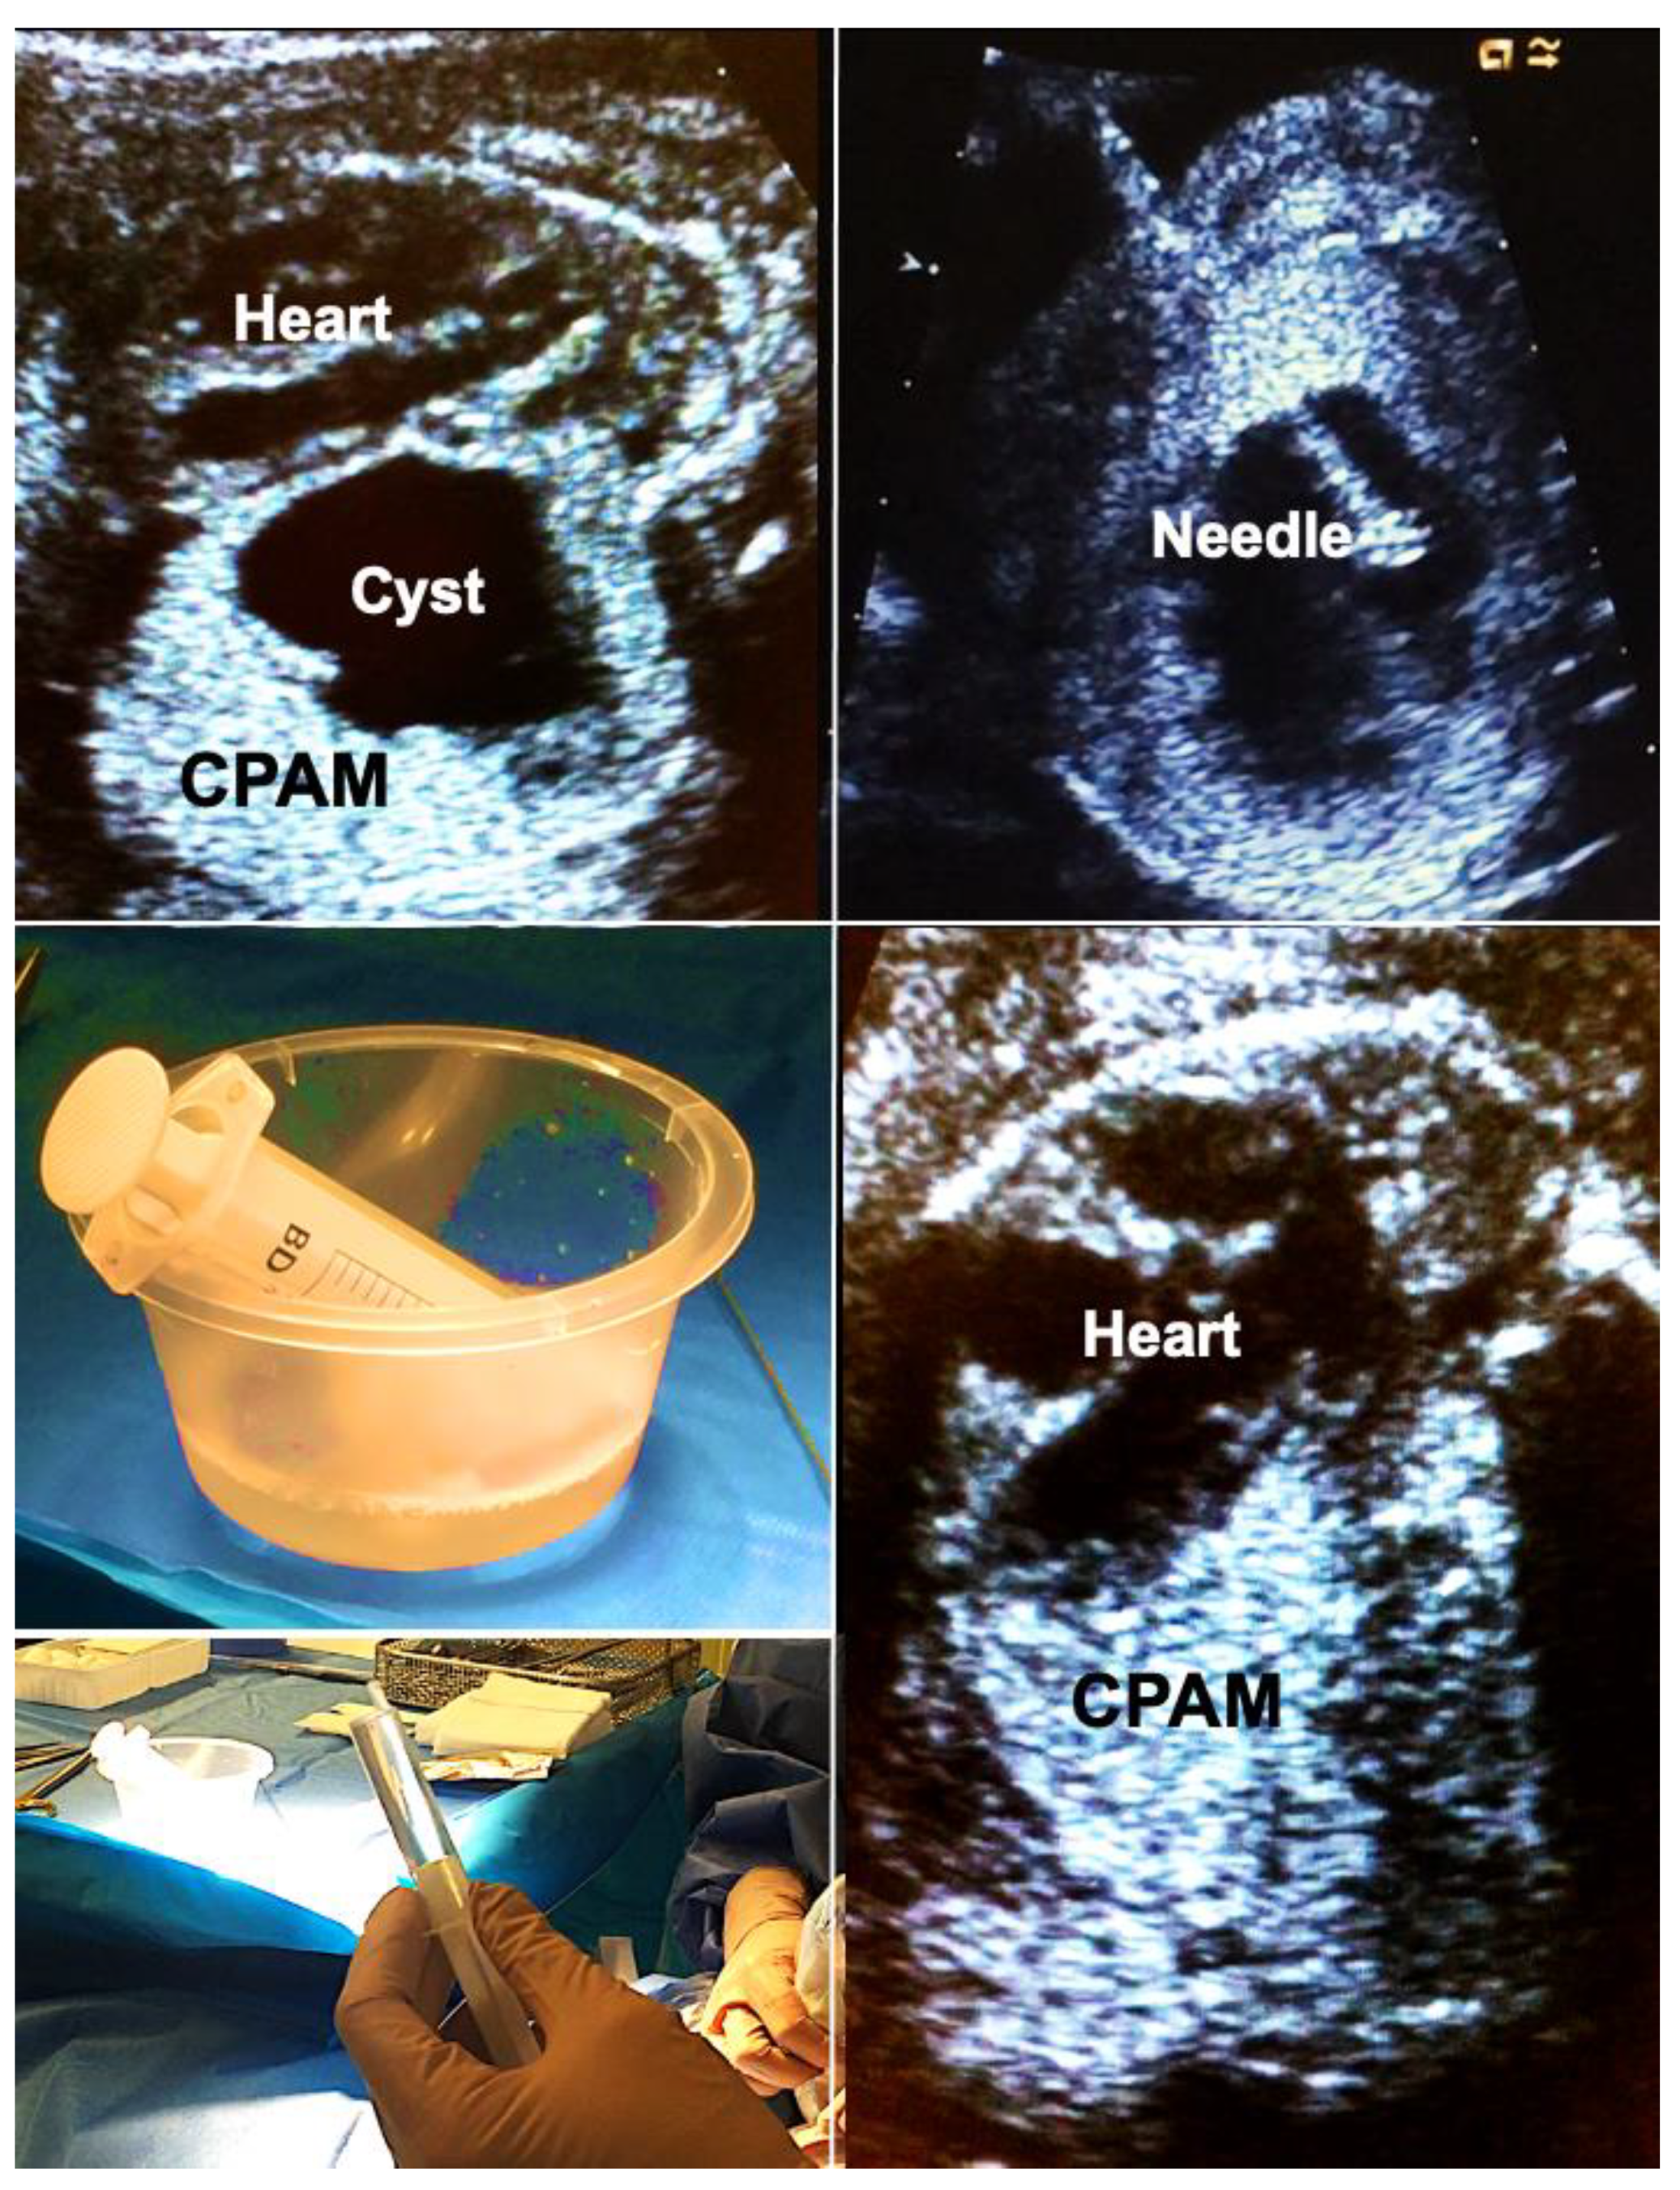

Figure 5.

Alcohol ablation in hydropic fetuses with congenital pulmonary airway malformations (CPAM) permits immediate and sustained volume reduction of large, life-threatening malformations. Top left—large left-sided CPAM with contralateral displacement and compression of the fetal heart. Top right—an 18-gauge needle has been placed into a large solitary cyst of the CPAM. Middle left—40 mL of fluid were aspirated from the cyst. Bottom left—then, the cyst is filled with 5 mL of pure ethanol. Bottom right—after 5 min, the ethanol is aspirated. Immediate improvement in cardiac filling can be observed. Hydrops usually resolves within days. In this case, the remainder of gestation remained uneventful. Survival to discharge was achieved after postnatal surgical removal of the CPAM.

Importantly, this approach may also be used to shrink large microcystic lesions which usually are the hardest to treat. In these cases, it is important to consider that the instilled amount of ethanol cannot be withdrawn. Therefore, only very small volumes of 0.1–0.2 mL ethanol have to be used. These must be instilled at multiple locations within the malformation, minimizing the risk of ethanol spillage into the pleural cavity, which could disturb the normal development of the fetal chest wall. This has been the only complication of ethanol ablation we have observed in one of our survivors. Other groups with experience of sclerotherapy with 5% ethanolamine oleate report that its intravascular injection should be avoided because it may result in cardiac necrosis [55,56].